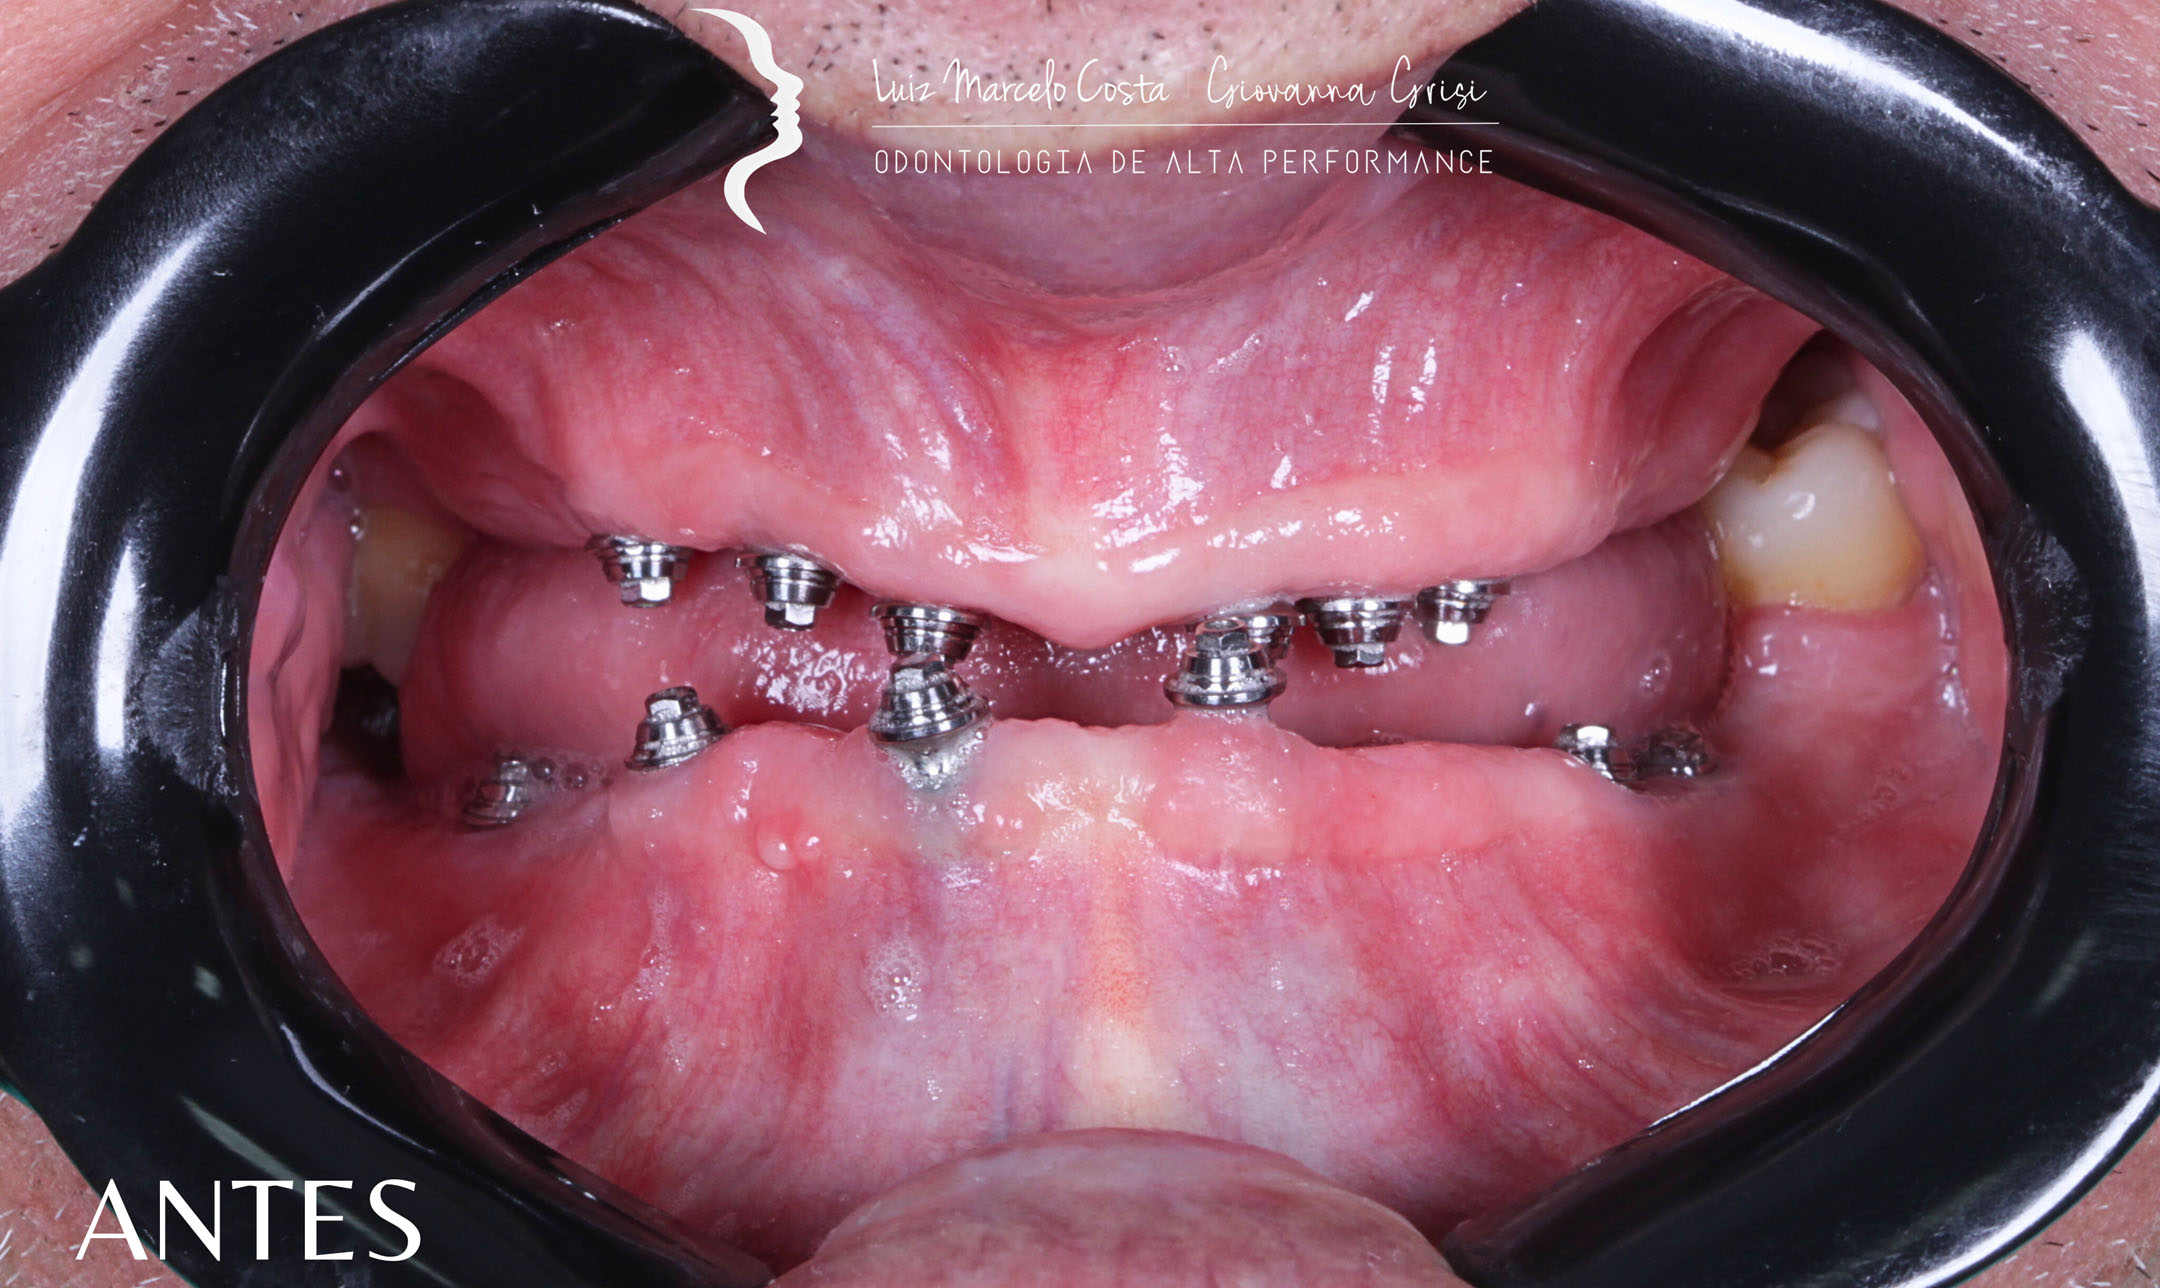

usados para substituir dentes perdidos. Implantes são fixados no osso como raízes dentárias, enquanto próteses são dispositivos que restauram a função e estética dos dentes ausentes.

usados para substituir dentes perdidos. Implantes são fixados no osso como raízes dentárias, enquanto próteses são dispositivos que restauram a função e estética dos dentes ausentes.

É uma prótese total fixada por pinos de implante, oferecendo uma solução definitiva para quem busca conforto e segurança ao falar, mastigar e sorrir.

Estrutura feita de titânio, semelhante a uma raiz dentária, posicionada cirurgicamente abaixo da margem gengival. Por ser fixo e unitário, também proporciona benefícios à saúde bucal em geral.